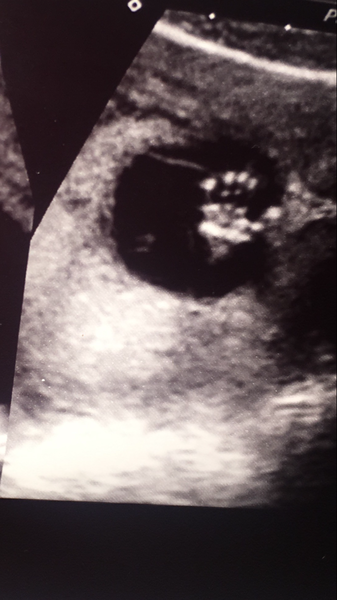

Wow have just caught up, congratulations everyone on your healthy scans! I was so scared about mine, I was distraught today going in, but all was fine and we got to watch baby for about an hour because we had a trainee sonographer and baby wasn't playing ball so I had to keep jumping around, being tipped up, rocked side to side, coughing etc! Until they could take all the measurements. Measuring bang on what we thought, 14 weeks today, and they gave us 6 pics for free instead of the standard 3 that we are meant to pay for because I was such a snivelling mess lol. So happy. We got a freaky X Files style hand pic too!

@Hazandduck you have such beautiful scan photos!

Amazing photos haz! It's like the baby is saying 'oi, stop prodding!'Grin

Thank you Mrs I can't stop staring at them, it kind of weirds me out to think of these tiny hands inside me! Haha it really was saying "talk to the hand!" X

Lovely scan Haz x

@Hazandduck what a brilliant picture.